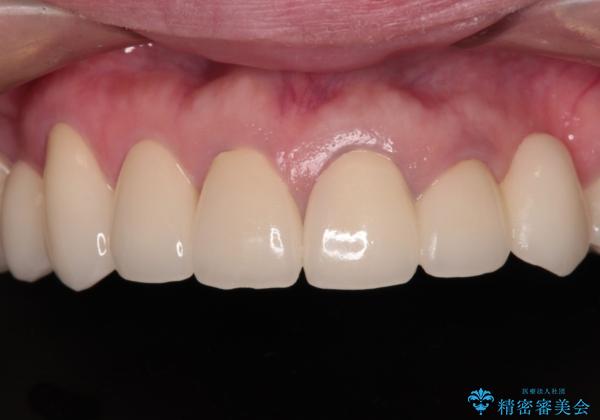

- 他院で矯正治療を終えたものの、むし歯や欠損部の治療が進められないとのことで来院された患者様です。

欠損部や、銀歯やむし歯の大きな歯はセラミッククラウンやブリッジに、小さいむし歯はセラミックインレーにて治療を行うこととしました。

歯肉の状態がとても、短期間でスムーズに治療を終えることができました。